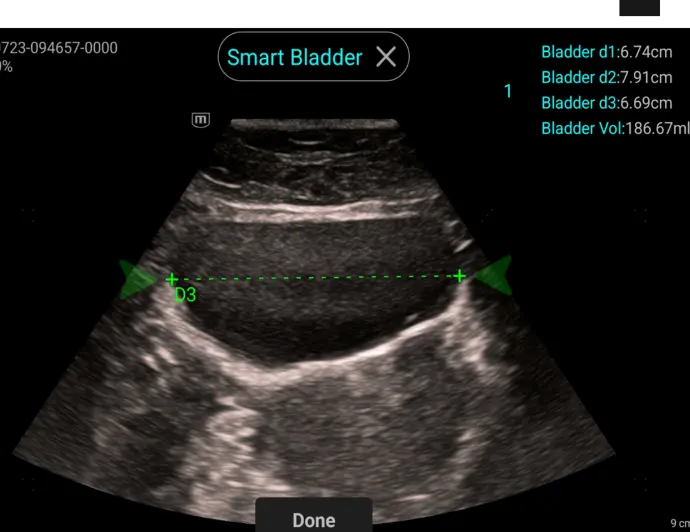

Smart Bladder

Aвтоматично измерване на 3те размера и калкулиране на обема на пикочния мехур